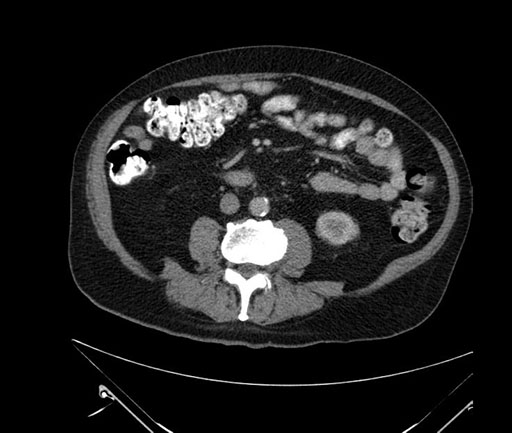

Whipple (pancreaticoduodenectomy) [case 7]

Axial - stented